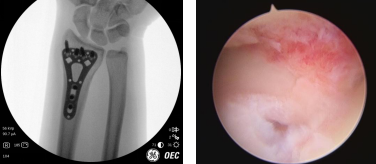

“我是一個耐痛力挺強的人,摔傷后我真覺得左手腕疼得受不了”,術前檢查顯示其左橈骨遠端骨折。當天,齊偉亞主任手術團隊為楊女士進行了“關節(jié)鏡輔助下左橈骨骨折復位內固定術”,術中,手術團隊在關節(jié)鏡下觀察手腕內部的情況,將碎裂的關節(jié)面拼接、復位和內固定。手術切口很小,不到2cm,還做了美容縫合。齊主任做完手術后沒有進行石膏固定,關節(jié)鏡微創(chuàng)病房都備有早期康復器材,患者術后第二天就可以在醫(yī)師指導下進行早期康復鍛煉。

術中

術后即刻(左圖)微創(chuàng)小切口(右圖)